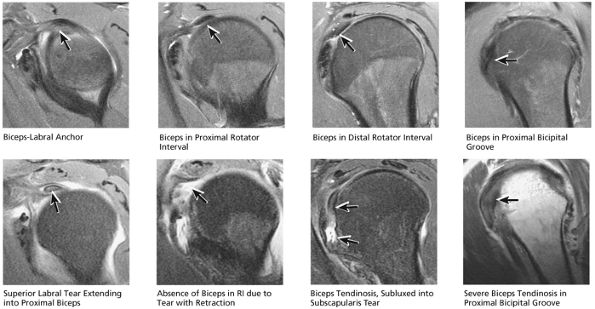

Biceps tendon and pulley

the bicipital groove. The sagittal plane is useful in identification of tendinosis of the proximal biceps tendon both within the rotator interval and at the proximal bicipital groove. Complete tears with retraction of the biceps tendon into the bicipital groove are displayed as absence of the biceps tendon within the rotator interval.

stripped from its lesser tuberosity attachment. However, because of an intact connection with the transverse humeral ligament, which connects the subscapularis tendon to the greater tuberosity, the tendon fibers appear to course in continuity without retraction. Proximal biceps tendon and subscapularis tendon pathology commonly coexist, since the pathogenesis of tendinosis and tears of both tendons are interrelated.